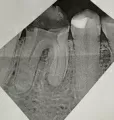

• Снимок не очень чёткий. Необходим осмотр и прицельный рентгеновский снимок 46 зуба, так как там стоит пломба больших размеров. Корневые каналы пролечены некачественно, потому что пломбировочный материал не прослеживается во всех каналах, они обтюрированы не плотно, то скорее всего есть воспалительный процесс за верхушкой корня зуб, что и вызывает у Вас постоянные боли. Прокон читать далее